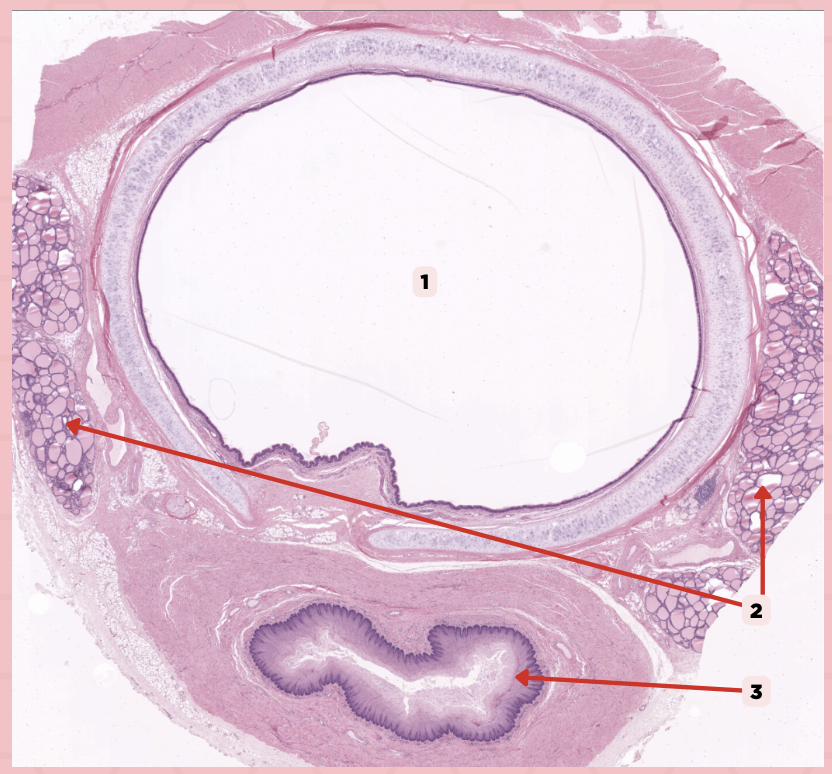

It is a large ovoid space that occupies the center of the trachea.

Lumen

Identify the structure labeled as 1.

Thyroid Gland

Identify the structure labeled as 2.

Esophagus

Identify the structure labeled as 3.

Ciliated Pseudostratified Columnar Epithelium

What is the epithelium of no. 3?

MALT